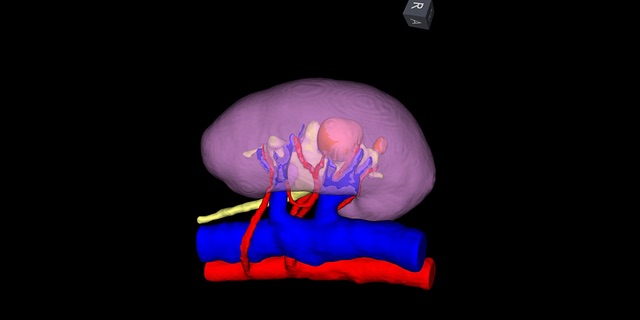

- Using your high-resolution images to create a 3D digital model of your kidney with IRIS™ -- for unparalleled surgery planning and guidance

We are the first of two centers in the U.S. to create a 3D digital model of your kidney for surgery planning and for navigation during tumor removal.

Our surgeons plan a roadmap for your surgery by visualizing the tumor in relation to surrounding structures in your kidney. Surgeons then use a real time image and align it with the intraoperative view for guidance from the robot’s console.

This technology has enabled some patients who would have had an entire kidney removed instead to have only the tumor removed while leaving remaining, functioning kidney tissue in place.

- Advanced 3D Kidney Modeling: We are the first of two centers in the U.S. to create a 3D digital model of your kidney for surgery planning and for navigation during tumor removal.